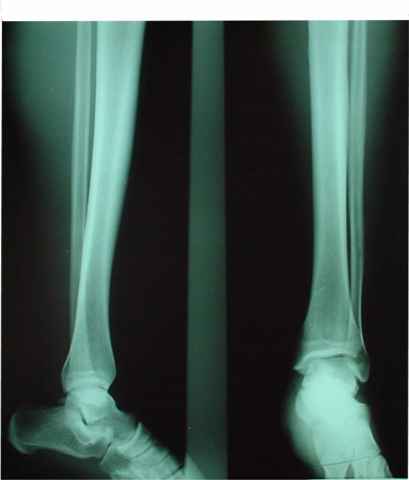

No lesiones Óseas